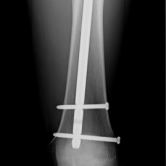

Röntgenbilder